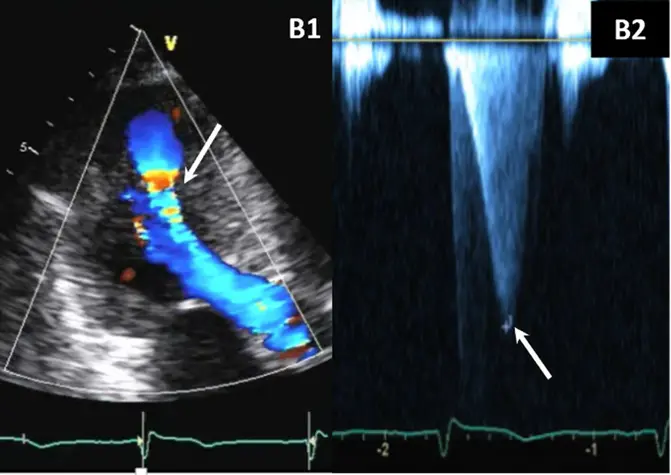

- midventricular obstruction (MVO)

- an important subtype of HCM to recognize as it may result in refractory symptoms and be associated with an increased risk of ventricular arrhythmias, mortality, and LV aneurysm (apical aneurysms often?) with or without thrombus.

- usually related to hyperkinesia of the mid-LV cavity → apposition of hypertrophied mid-septum and hypertrophied papillary muscles

- Color-flow Doppler shows turbulence at mid-ventricular level

- CWD typically shows a narrow, late-peaking systolic velocity (“ice pick” appearance)